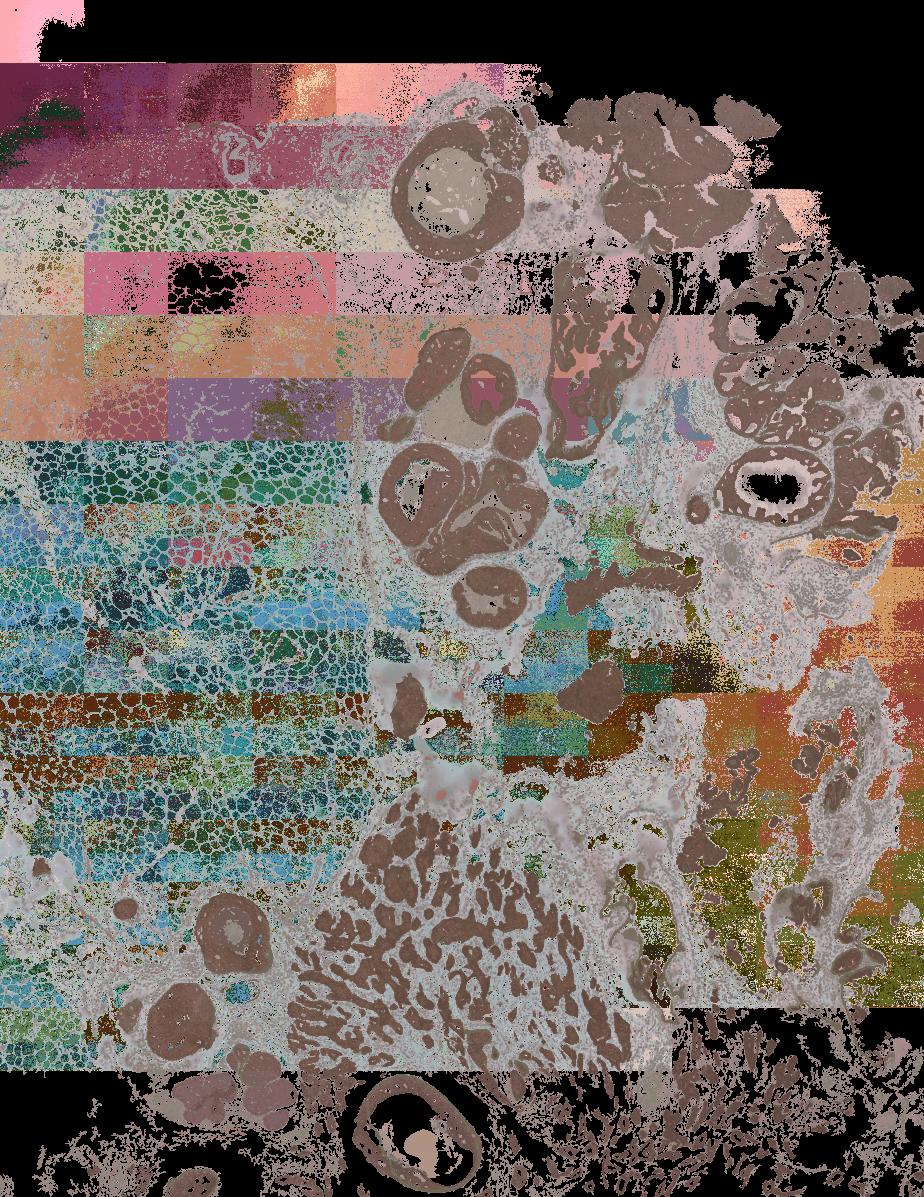

To study the spatial interactions among cancer and non-cancer cells1, we here examined a cohort of 131 tumour sections from 78 cases across 6 cancer types by Visium spatial transcriptomics (ST). This was combined with 48 matched single-nucleus RNA sequencing samples and 22 matched co-detection by indexing (CODEX) samples. To describe tumour structures and habitats, we defined ‘tumour microregions’ as spatially distinct cancer cell clusters separated by stromal components. They varied in size and density among cancer types, with the largest microregions observed in metastatic samples. We further grouped microregions with shared genetic alterations into ‘spatial subclones’. Thirty five tumour sections exhibited subclonal structures. Spatial subclones with distinct copy number variations and mutations displayed differential oncogenic activities. We identified increased metabolic activity at the centre and increased antigen presentation along the leading edges of microregions. We also observed variable T cell infiltrations within microregions and macrophages predominantly residing at tumour boundaries. We reconstructed 3D tumour structures by co-registering 48 serial ST sections from 16 samples, which provided insights into the spatial organization and heterogeneity of tumours. Additionally, using an unsupervised deep-learning algorithm and integrating ST and CODEX data, we identified both immune hot and cold neighbourhoods and enhanced immune exhaustion markers surrounding the 3D subclones. These findings contribute to the understanding of spatial tumour evolution through interactions with the local microenvironment in 2D and 3D space, providing valuable insights into tumour biology.